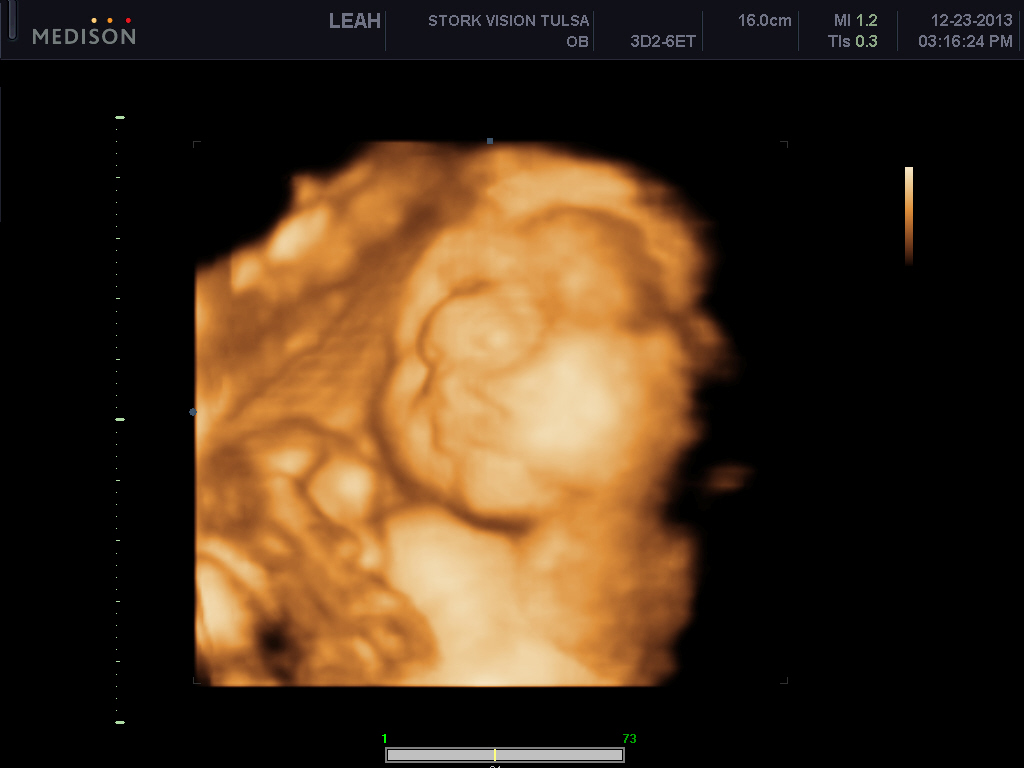

I want to AW my sons 3d ultrasound! :) PIP heavy

He's freaking adorable! These are my favs out of about 70 pictures..

Look at those cheeks!